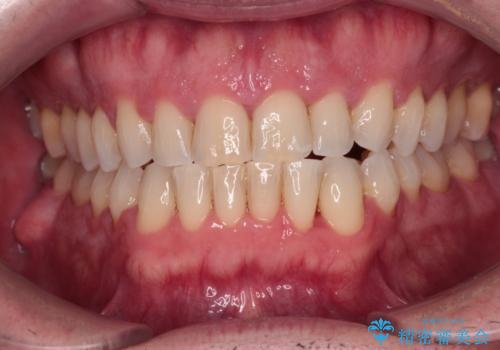

[ 前歯開咬 ] 前歯が噛んでいない マウスピース矯正治療

担当医 大元洋佑

![[ 前歯開咬 ] 前歯が噛んでいない マウスピース矯正治療の症例 治療前](https://seimitsushinbi.jp/wp/wp-content/uploads/2022/11/IMG_4669-500x350.jpg?v=1668218426)

![[ 前歯開咬 ] 前歯が噛んでいない マウスピース矯正治療の症例 治療後](https://seimitsushinbi.jp/wp/wp-content/uploads/2022/11/IMG_2488-500x350.jpg?v=1668218373)